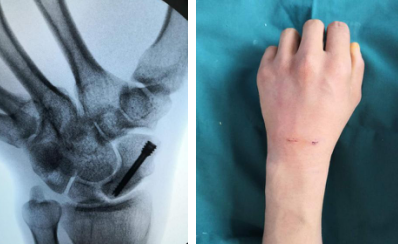

5月7日,齐主任手术团队为小刘进行了“机器人导航+关节镜辅助下左舟骨骨折复位取髂骨植骨内固定术”。术中关节镜探查见:左舟状骨骨折端部分骨质硬化,周围滑膜增生,髓腔内部分坏死。关节镜下用一次性磨钻,磨除骨折两端硬化骨质及坏死骨质至骨折端有新鲜血液渗出,关节镜下一次性刨削器刨除滑膜组织。再于右侧髂骨处开窗式取松质骨,将准备好的松质骨剪成小块儿通过关节镜套筒植入左舟骨骨折端缺损处。完成植骨后,机器人导航下予以精准3D定位,螺钉内固定。手术顺利,全程3个多小时。

机器人精准打钉(左图)术后微创切口(右图)